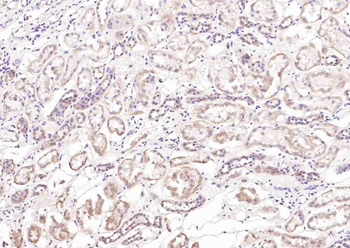

TSPO/PBR Rabbit Polyclonal Antibody

FC, IF, IHC-Fr, IHC-P

应用稀释比例:IHC-P=1:100-500, IHC-F=1:100-500, IF=1:100-500, Flow-Cyt=1ug/test